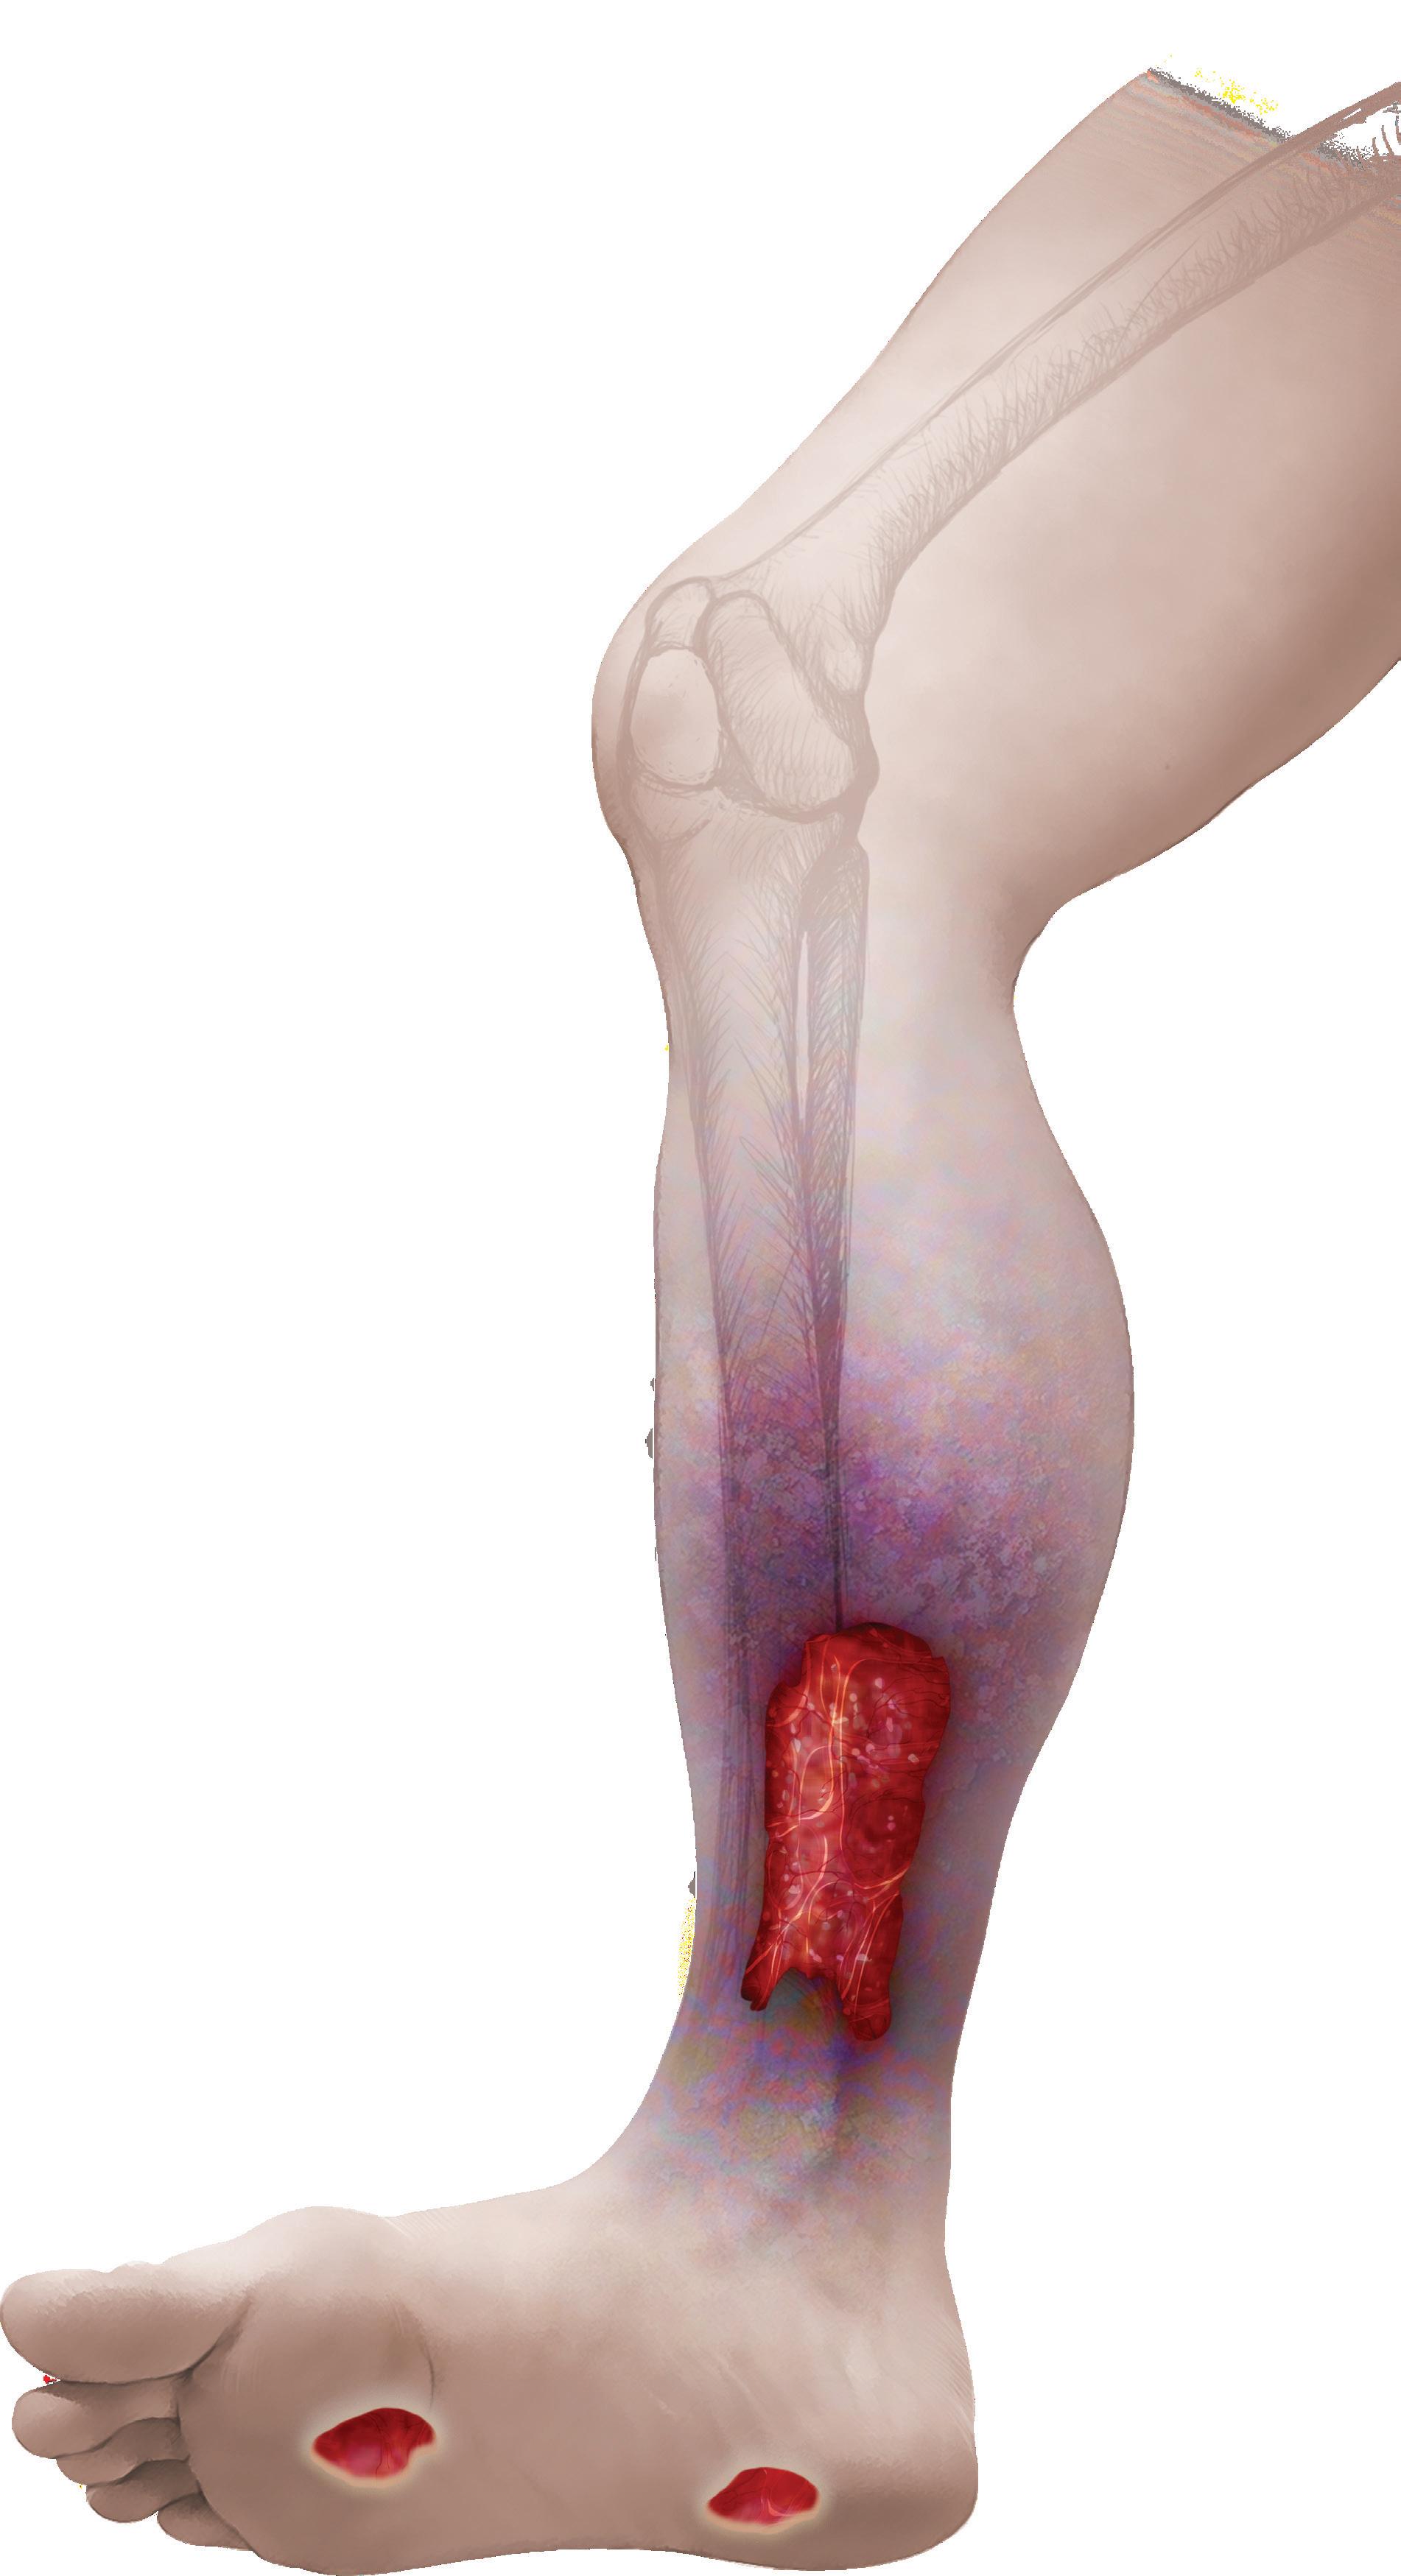

AMNIOFIX® and AMNIOEFFECT®: Placental-based sheet allografts provide a protective barrier to support the healing cascade and the development of granulation tissue.

AXIOFILL®: Acellular human placental ECM particulate used in the replacement or supplementation of damaged or inadequate integumental tissue.

RCT Outcomes with DHACM Scan to learn more or contact us: 888.543.1917 customerservice@mimedx.com DHACM = Dehydrated Amnion/Chorion Membrane, DFU = Diabetic Foot Ulcer, VLU = Venous Leg Ulcer, SOC = Standard of Care * 2x = based on mean time and 3.8x = based on median time, ^ Per Protocol group VLUs DFUs defect closure vs. SOC at 16 weeks3,4^ 1.6x rate of

2x to 3.8x faster defect closure vs. SOC1,2* Patents and patents pending see: www.mimedx.com/patents. AMNIOFIX, AMNIOEFFECT, AXIOFILL, and MIMEDX are trademarks of MIMEDX Group, Inc. ©2023 MIMEDX Group, Inc. All Rights Reserved. www.mimedx.com US-AC-2300002 v1.0 REFERENCES: 1. Zelen CM, et al. Int Wound J. 2013;10(5):502-507. 2. Zelen CM, et al. Int Wound J. 2015;12(6):724-732. 3. Bianchi C, et al. Int Wound J. 2018;15(1):114-122. 4. Bianchi C, et al. Int Wound J. 2019;16(3):761-767. THINK ASAP. Before

defects lead to amputation, Advanced Surgical Allograft Products

limb